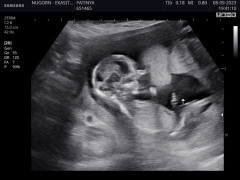

แม่ๆทีม มีนา 67 มาอวดภาพอัลตราซาวเจ้าตัวน้อยของแม่ๆหน่อยค่า แม่บ้านไหนรู้เพศเจ้าตัวน้อยแล้วบ้างค่า

บ้านนี้ท้อง 2 ยังตื่นเต้นเหมือนเดิมเลยค่า กำหนดคลอด 15 มีนา 67 / 11w6d